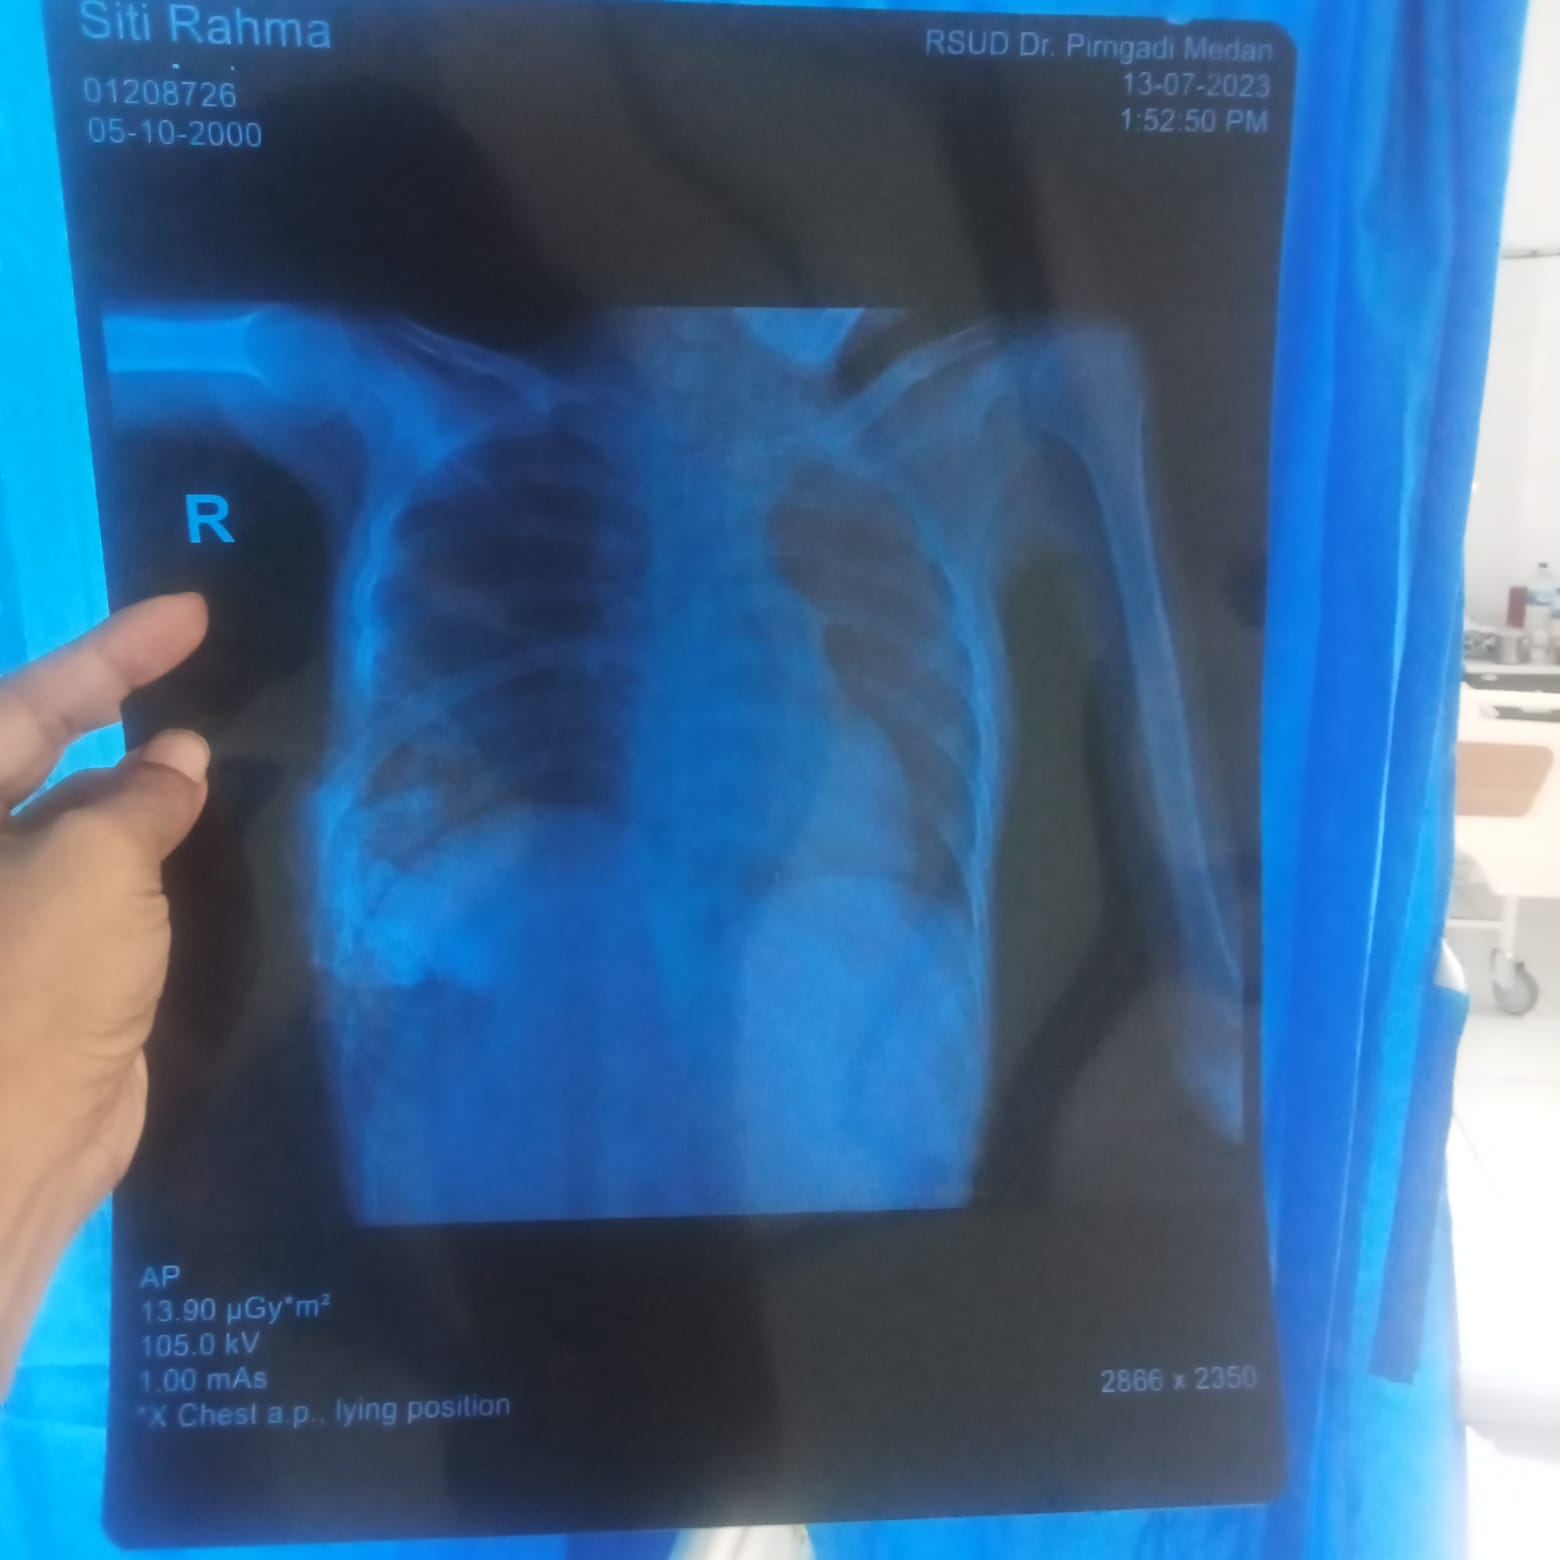

Aku Siti Rahma (23th) dari Medan Johor - Sumatera Utara. Di usianya yang masih terbilang muda ini, aku harus menjalaninya dengan sangat menyakitkan dan cuma terbaring lemah di kasur saja. Ini tumor di payudara yang kuderita sudah semakin parah.

Tumor Siti Sudah Menyebar Ke Jantung Dan Tulang

Aku cuma mau cerita tentang kondisiku saat ini. Juni lalu, aku sudah menjalani operasi bedah tumor di Rumah Sakit Murni Teguh.

Aku juga harus sering ganti perban, karena tumorku selalu bernanah bahkan berulat. Makanya, aku harus pergi kontrol seminggu dua kali.

Belum lagi aku masih harus membeli kebutuhan sehari-hariku seperti popok, underpad, tisu, dan susu. Perawatanku benar benar serius kata dokter, karena tumornya sudah menyebar ke jantung maupun tulang.